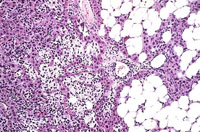

An Ito cell tumor that has replaced much of the normal hepatic parenchyma without distorting the normal contour of the liver; higher magnification shows fat-filled and stellate cells in the hepatic sinusoids.